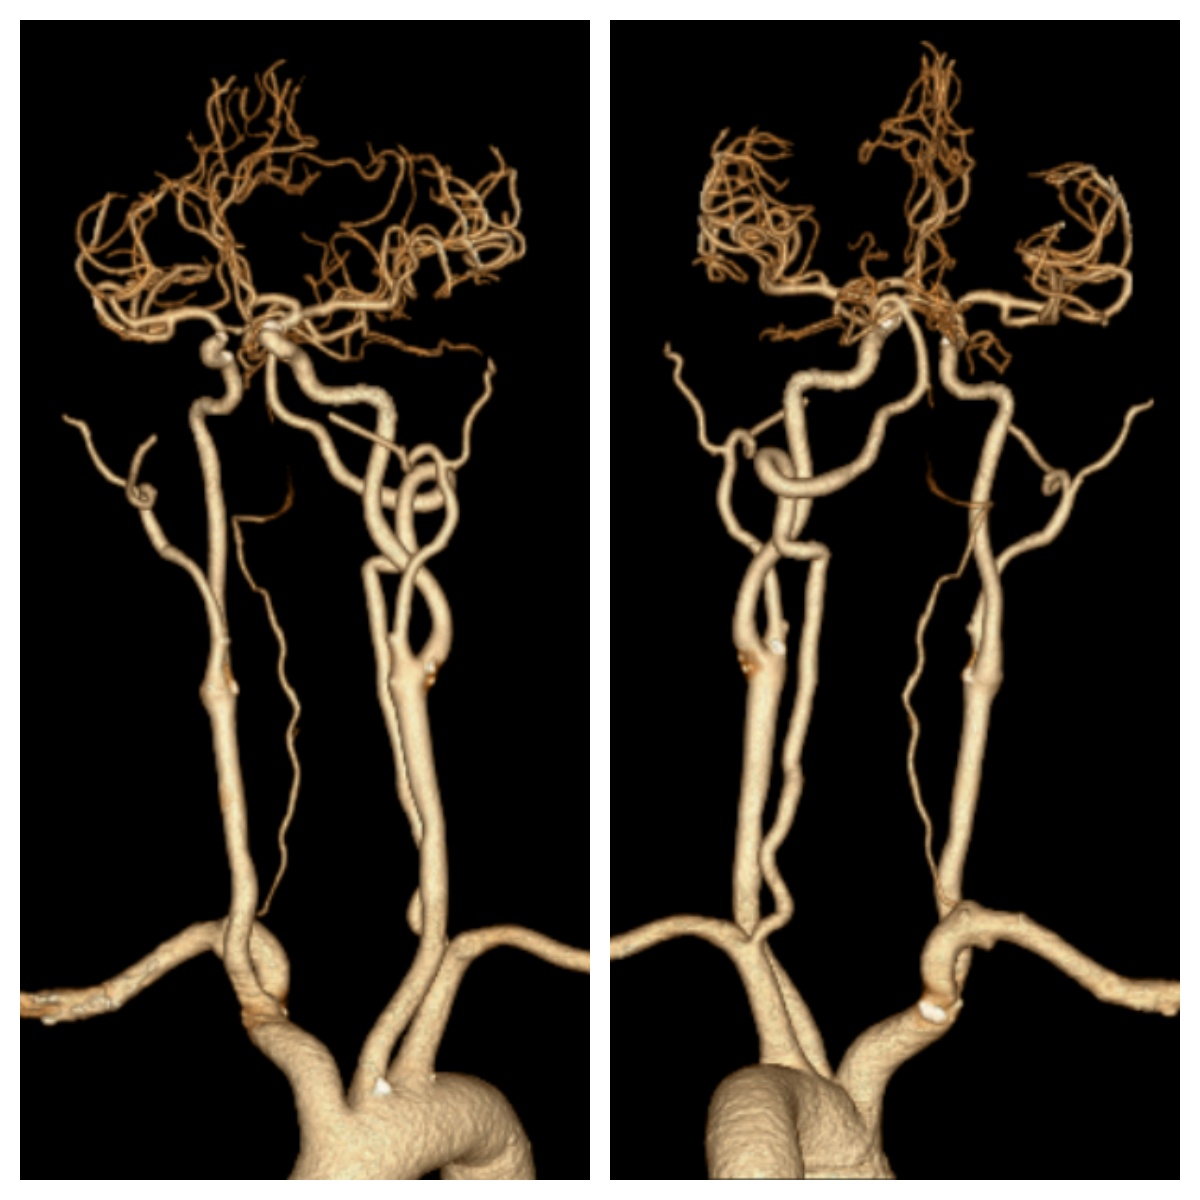

73岁男患,因“右侧肢体无力伴不能言语1小时余”入院;既往有脑梗死病史,未口服脑卒中二级预防药物治疗。入院时心电图提示心房颤动;急诊查颅脑CT排除颅内出血,且左侧大脑中动脉高密度征;急诊查头颈部CTA提示左侧大脑中动脉M1段闭塞,急诊查头颅CTP提示左侧大脑半球低灌注。考虑心源性脑栓塞,急诊行静脉溶栓桥接机械取栓治疗,最终病人恢复正常出院。

术后复查CTA